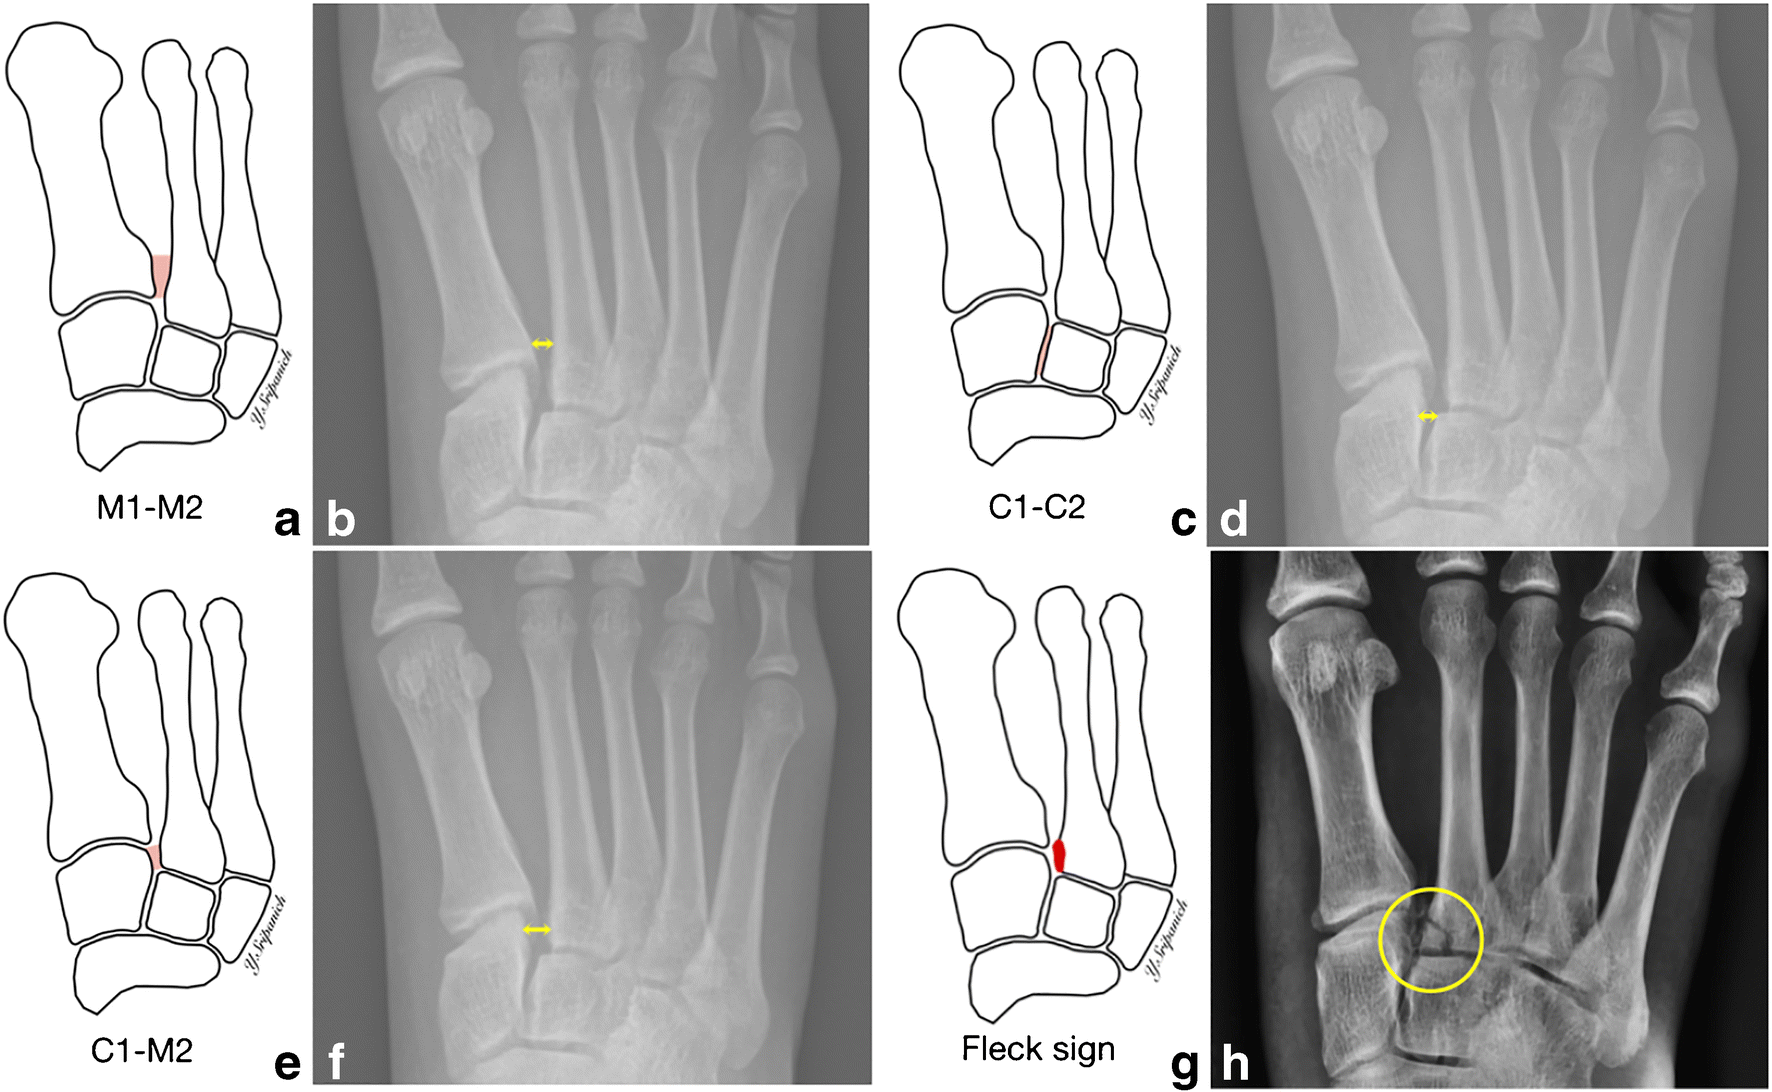

Direct forces include a crush injury MVA or industrial or a direct blow. Lisfranc injuries are commonly asked about in FRCS Orthopaedic trauma vivas. Diagnosis is confirmed by radiographs which may show widening of the interval between the 1st and 2nd ray.

Figure 3 Imaging In Lisfranc Injury A Systematic Literature Review Springerlink

Anteroposterior Foot X Ray Demonstrating Lisfranc Injury The Medial Download Scientific Diagram